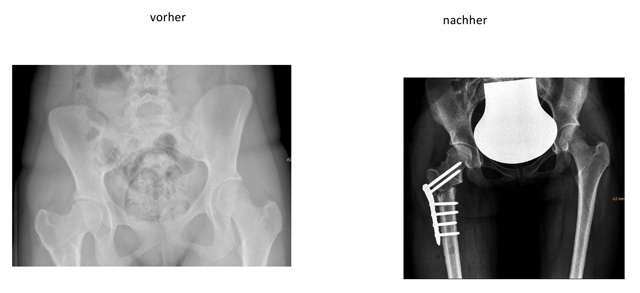

Die Proximale Femur Osteotomie bezeichnet die Achskorrektur am oberen Teil des Oberschenkelknochens. Meist sind Drehfehler (Knochentorsion) und Abweichungen des Schenkelhalses in X-Richtung Grund für die Operation.

Die häufigst durchgeführte Technik der Proximalen Femur Osteotomie geschieht mittels chirurgischem Zugang von der Außenseite des Oberschenkel. Nach Durchtrennung des Knochens und Neupositionierung in der gewünschten Position wird die erzielte Korrektur mittels Schrauben-Platten-System gehalten, ähnlich wie bei einem Knochenbruch.

Bei speziellen Indikationen, v.a. nach chirurgischen Vorverhandlungen, kann eine Korrekturosteotomie des Schenkelhalses auch mit gleichzeitiger Verlängerung des Schenkelhalses notwendig werden.

Intertrochantäre Ostetomie